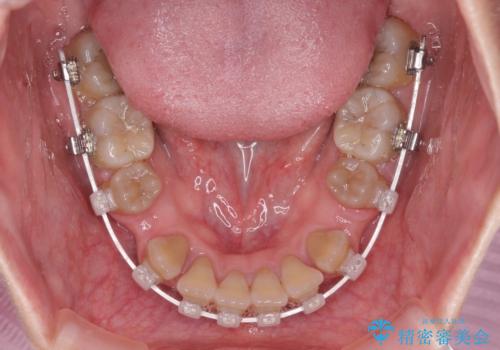

八重歯とクロスバイト 目立たないワイヤー装置での抜歯矯正

- 八重歯や前歯のデコボコを気にして来院された患者様です。

歯列が前方に傾斜しており、デコボコが強かったため、上下左右第一小臼歯4歯を抜去し、ワイヤー装置による矯正治療を行うこととしました。

上下の正中がずれていましたが、抜歯矯正であったので、極力正中位置を合わせるように治療を進めて行きました。

顎間ゴムの使用などにより、正中位置を改善することができました。